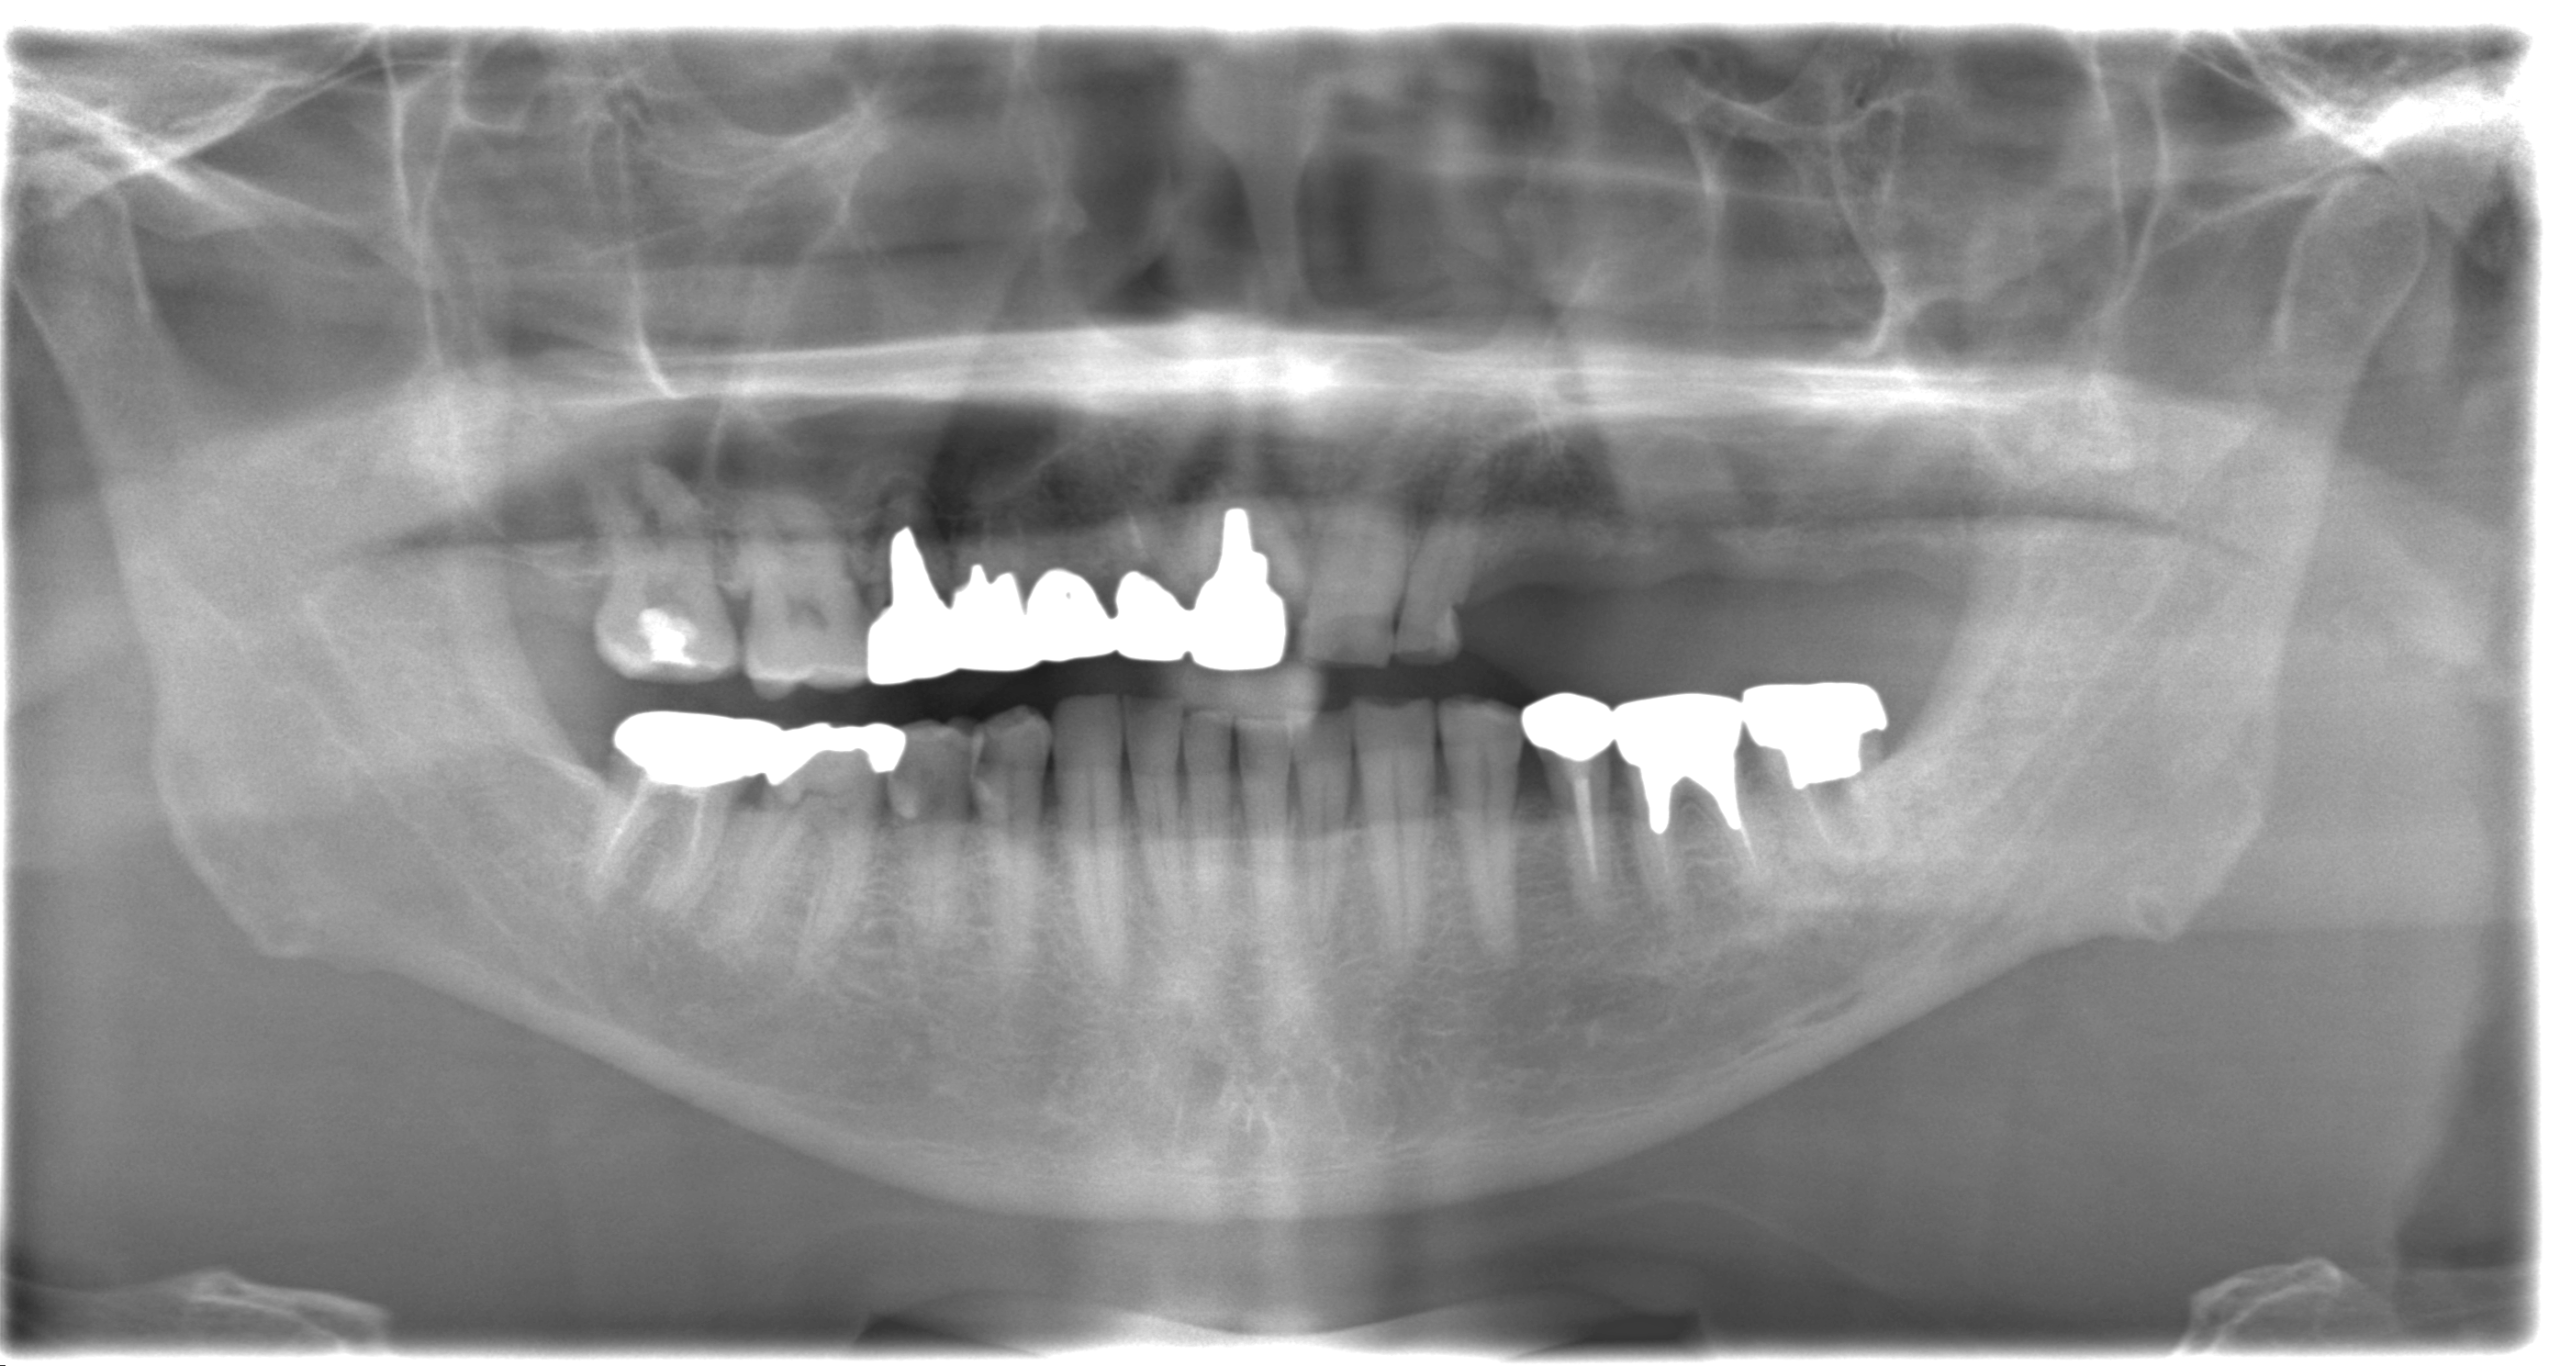

<After>

写真では上顎洞に骨が足されているのがわかります。

骨をしっかり足すことでインプラントを埋入することができました。